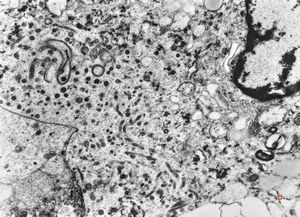

F, 72y. | carcinoid … metastasis to lymphonode